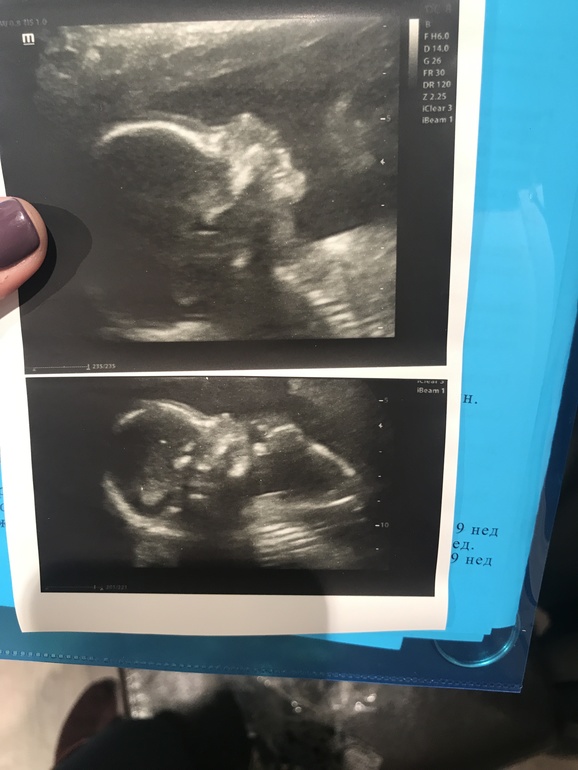

И на память, наше первое фоток пальчиком во рту😍Всем лёгкой беременности и родов 🤗😊